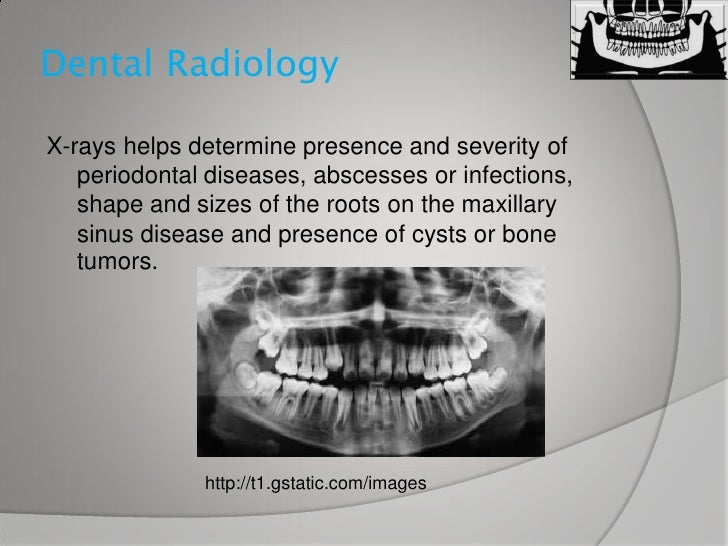

9 Amazing How To Read A Dental X Ray - A degree of magnification (around 8%) is. • radiographic interpretation is an essential part of the diagnostic process.

8 Skill How To Read A Dental X Ray. Why you need xrays x ray, patient education, dental decay underneath crowns and bridge work. This quick guide shows you some of what we see and what we are looking for. Treating problems before they get serious can save money, pain and sometimes even your life. How to read a dental x ray

Metal) let fewer beams pass through and the whiter the image appears in that area. Is designed to display most medical images: Finding and treating dental problems at an early stage can save both time and money. How to read a dental x ray

After the film has developed in a short time like a few minutes, your dentist can determine what needs to be done and the method of treatment. The head is towards the left. This exam requires little to no special preparation. How to read a dental x ray

It points out that the failure rate is up to 51% based on a study of 400 patients! It is easy to miss a fracture with only one view (see red circle). It is commonly performed by dentists and oral surgeons in everyday practice and may be used to plan treatment for dentures, braces, extractions and implants. How to read a dental x ray

Dental x ray film has the following characteristics: Dental x ray film has the following characteristics: Tmj problems such as slipped discs ( clicking or popping noises) or complete disc dislocation (can’t open your mouth very far) doesn’t How to read a dental x ray

This is the standard type of image that's used to look for cavities. Just a shaft view is not enough. Receptors can be vinyl film packets or digital sensors. How to read a dental x ray

The black areas are the soft objects such as decay and the nerves and blood.read more. The interpretation of a chest film requires the understanding of basic principles. How to read dental x rays infection. How to read a dental x ray

How to read x rays of teeth. Adequacy alignment aadi (anterior atlantodental interval) bdi (bsion dental interval) base of 4.2 out of 5 4.2 (11 ratings) 36 students created by dental hub last updated 4/2020 english english [auto] what you'll learn learn about why and how no. How to read a dental x ray

The head is at the far left. If positioning is not precise, a poor image can result. This is the standard type of image that's used to look for cavities. How to read a dental x ray

Due to this, hard tissues like the enamel and dentin will appear light in color. The type of image that your dentist orders will depend on what they need to check for. How to read a dental x ray